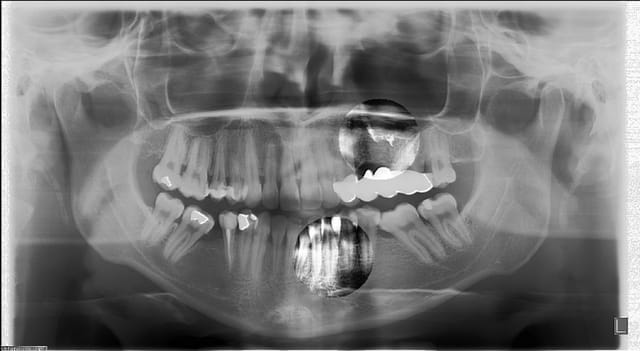

Ma planmeca donne ça:

Pano qcvlac - Eugenol

Heu... Je m'aperçoit que la patient a du bouger. Ce qui cause les déformations de la zone incisive inf. :-(